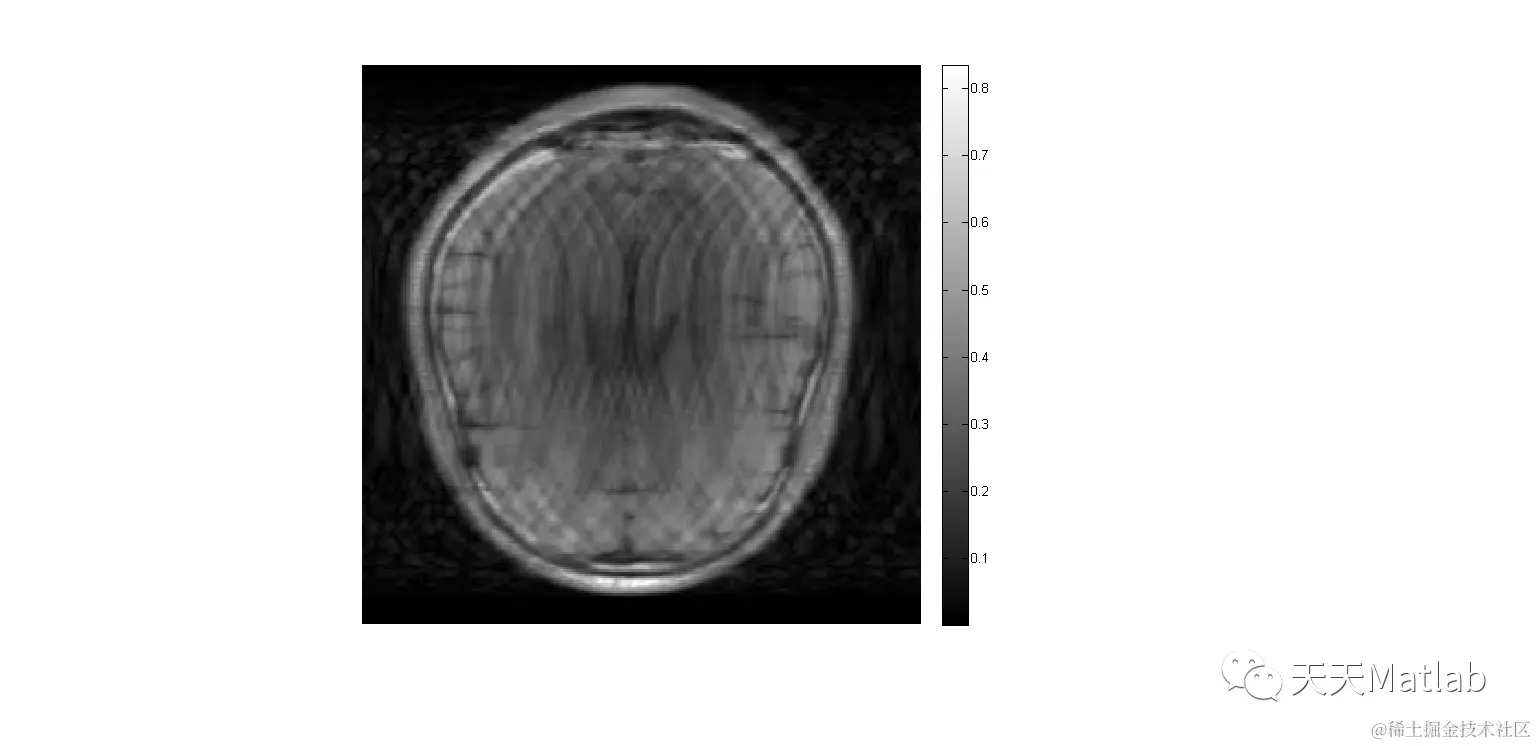

figure,imshow(abs(im1_Rec));title('Reconstructed image')